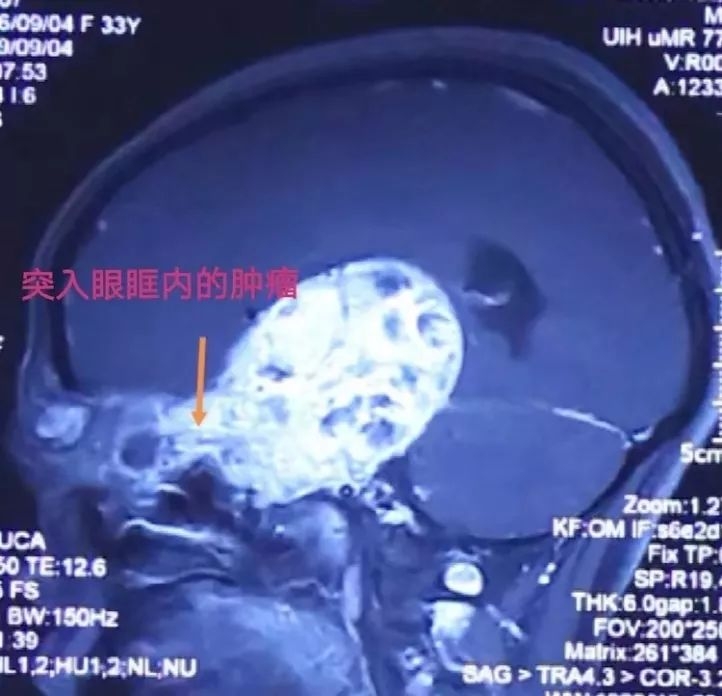

颅眶沟通性肿瘤切除手术

术前